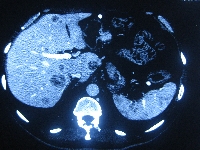

Πρόκειται για άνδρα ασθενή 58 ετών, ο οποίος υποβλήθηκε σε αξονική τομογραφία για επιγαστραλγία. Διαπιστώθηκε μάζα στην ουρά του παγκρέατος μεγέθους 5 εκατοστών, καθώς και πολλαπλές (περίπου 50) ηπατικές μεταστάσεις (εικόνες 1, 2). Βιοψία μίας από τις ηπατικές μάζες ανέδειξε νευροενδοκρινές καρκίνωμα καλής διαφοροποίησης. Ο ασθενής υποβλήθηκε σε ουραία παγκρεατεκτομή με σπληνεκτομή (εικόνα 3), αριστερή ηπατεκτομή μετά του 1ου τμήματος (εικόνα 4), τέσσερεις άτυπες δεξιές ηπατεκτομές και πολλαπλές κατευθυνόμενες (IOUS) εστιακές καταστροφές με μικροκύματα (εικόνα 5). Ογκομετρική αξονική την 7η μετεγχειρητική ημέρα ανέδειξε μείωση του μεταστατικού φορτίου σε ποσοστό > 90%. Κατόπιν, την 6η και 10η μετεγχειρητική εβδομάδα, ο ασθενής υποβλήθηκε σε διαδοχικούς υπερεκλεκτικούς (πρόσθιο και οπίσθιο) εμβολισμούς της δεξιάς ηπατικής αρτηρίας (εικόνα 6, απεικόνιση του πρόσθιου μετά από εμβολισμό του οπίσθιου τομεϊκού δεξιού αρτηριακού κλάδου). Οctreotide-scan τη 12η μετεγχειρητική εβδομάδα ανέδειξε απουσία ενεργών νευροενδοκρινών εστιών. Ο ασθενής λαμβάνει Sandostatin LAR εφ' όρου ζωής.